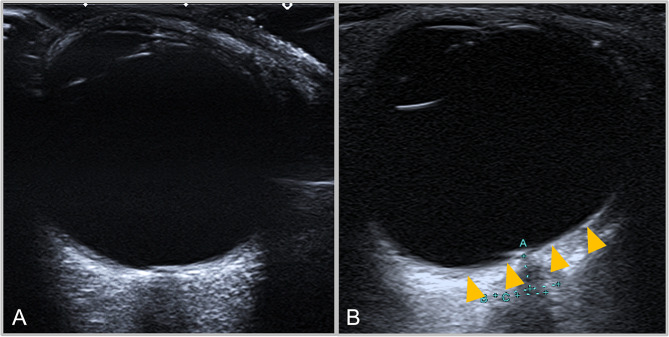

Methods: Consecutive IIH patients and healthy controls were enrolled in a prospective case-control study. Transorbital ultrasound was performed to assess the presence of PGF. For quantification of PGF, an angular measurement (PGA) was performed with the vertex centering the optic nerve at a predefined distance from the lamina cribrosa and angle legs tangentially aligned to the borders of the vitreous body. PGA measurements were compared between IIH patients and healthy controls. Additionally, the diagnostic accuracy of PGA measurements in detecting PGF was evaluated using ROC analysis.

Results: Thirty-one IIH patients (37.3 ± 12.3 years, 29 female) and 28 controls (33.3 ± 11.8 years, 21 female) were compared. PGF was present in 39% of IIH patients and absent in the control group. PGA3mm measurements significantly differed between IIH and controls (116.5° ± 5.5 vs. 111.7° ± 2.9; p < 0.001). A PGA3mm cutoff of ≥ 118.5° distinguished IIH patients from controls with 100% specificity, while retaining a sensitivity of 37.5%.